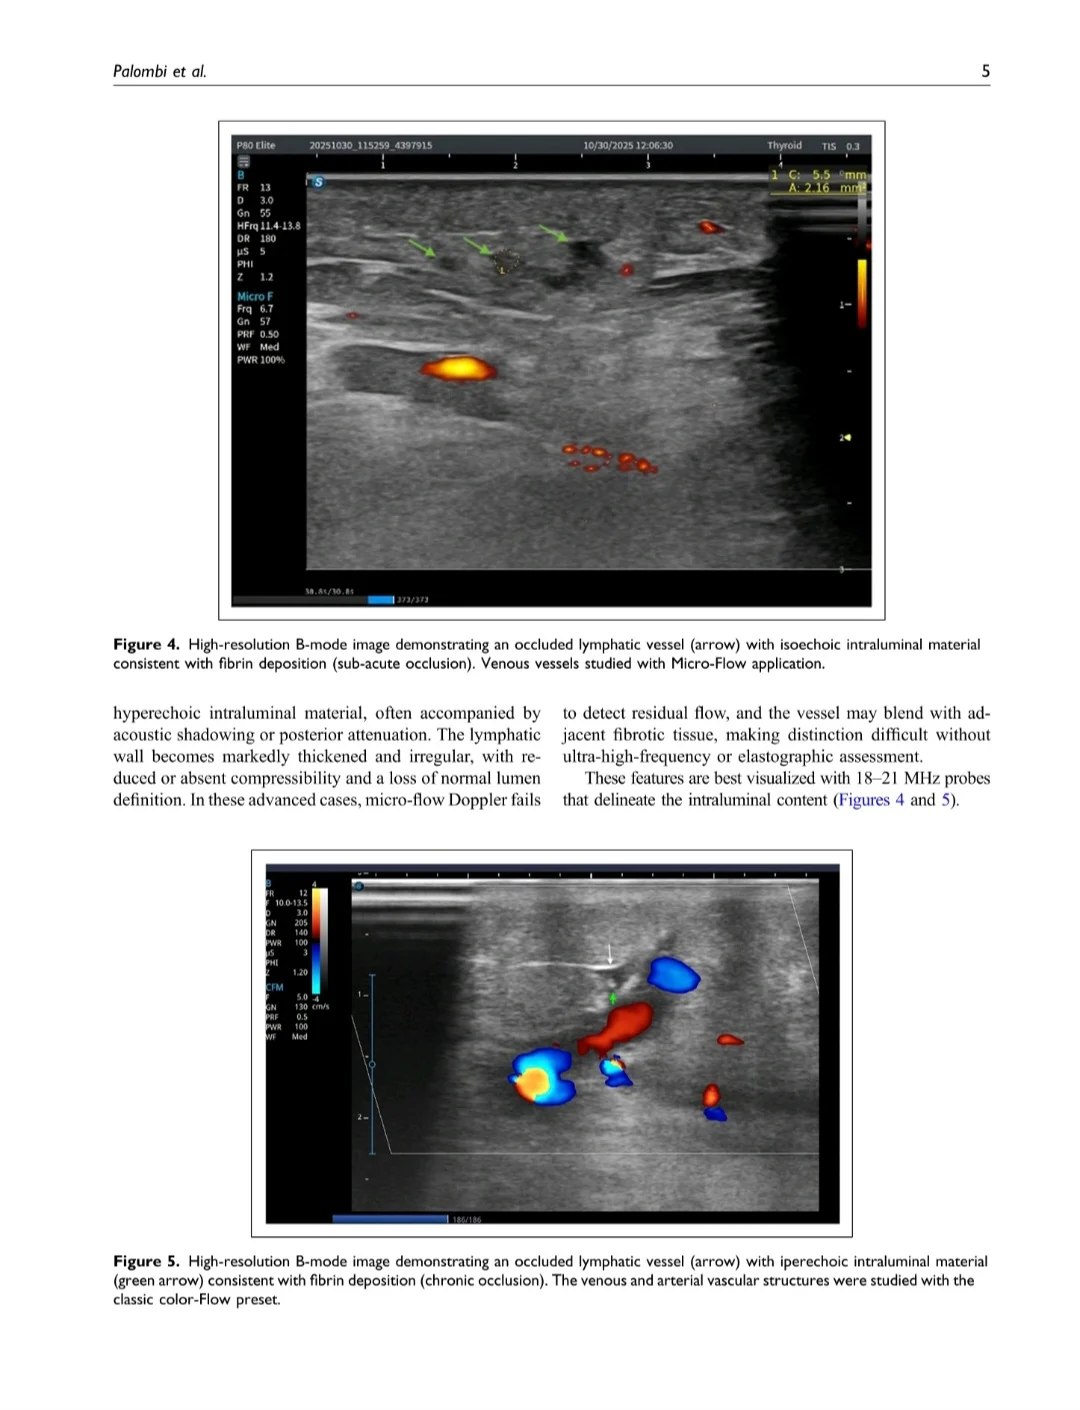

- High‑frequency imaging and micro‑flow presets can show intraluminal fibrinous plugs in chronically obstructed lymphatics, offering a window into irreversible damage

- The examinations used high‑frequency probes plus micro‑flow and elastography with AI‑assisted image optimization to enhance lymphatic and soft‑tissue visualization and reduce operator dependency. The authors utilized transducer frequencies from 18-21 MHz for superficial lymphatic channels and skin layers and ultra-high frequencies 48-70 MHz for depicting even smaller lymphatic vessels